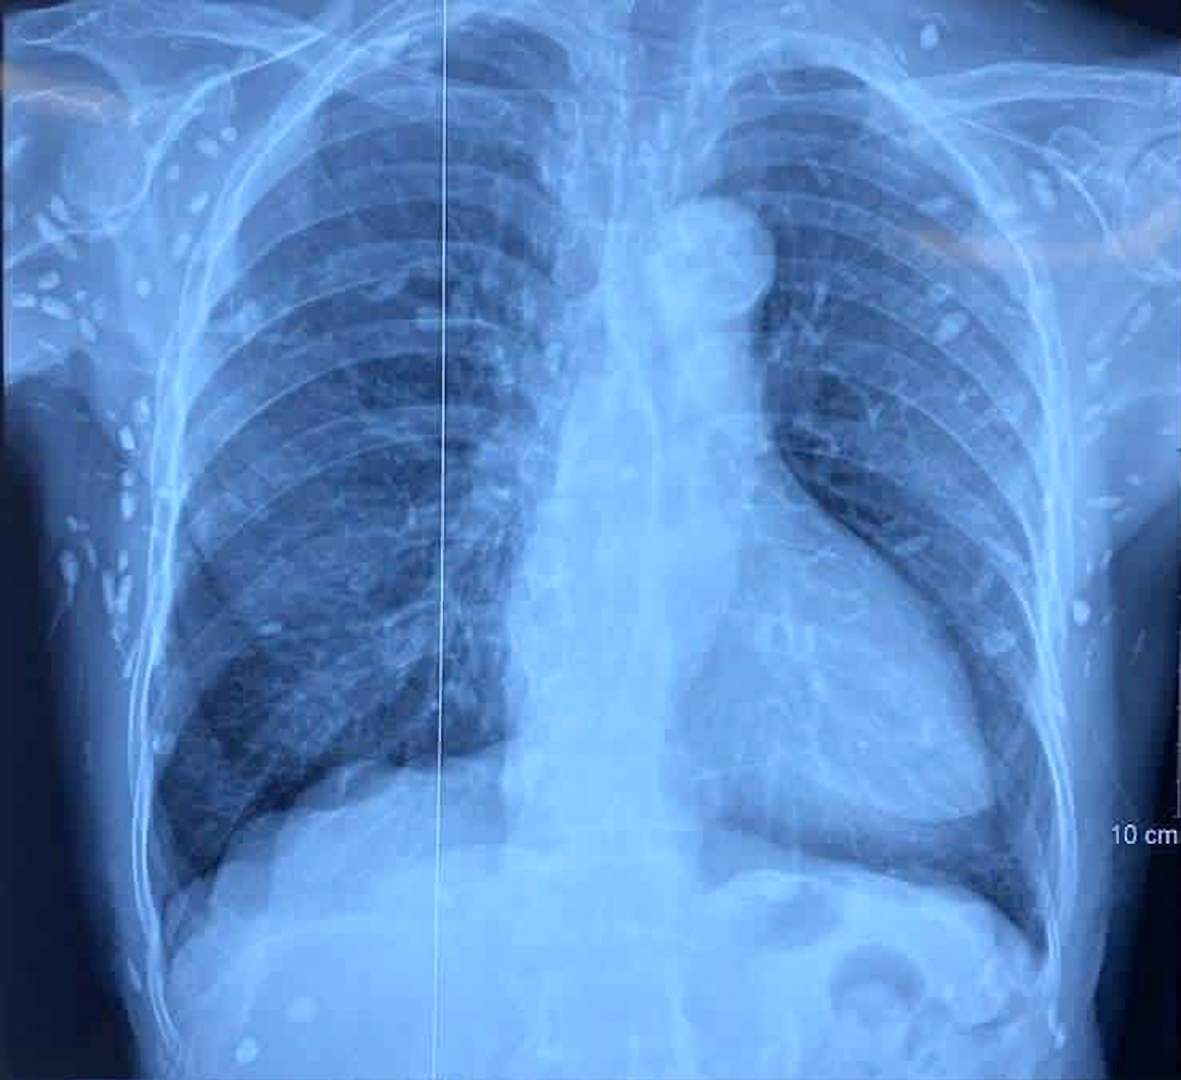

Chụp X-quang xương đùi, CT-scan ngực tầm soát tổn thương ở cơ quan khác thì phát hiện vô số nang sán dải còn sống hoặc đã bị hóa vôi "ẩn nấp" trong não, nhu mô phổi và trong da, cơ trên toàn bộ cơ thể.

Nhiều nốt cản quang dưới da thành ngực - bụng và chi trên - Ảnh: BVCC